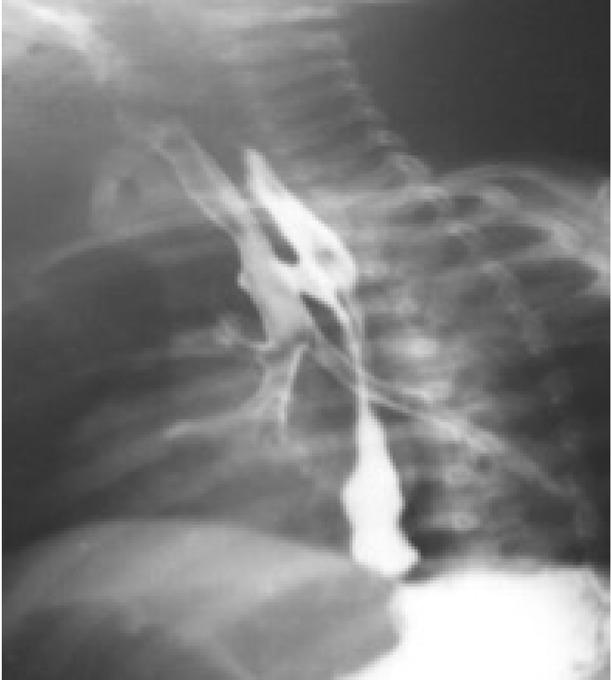

Figure 2